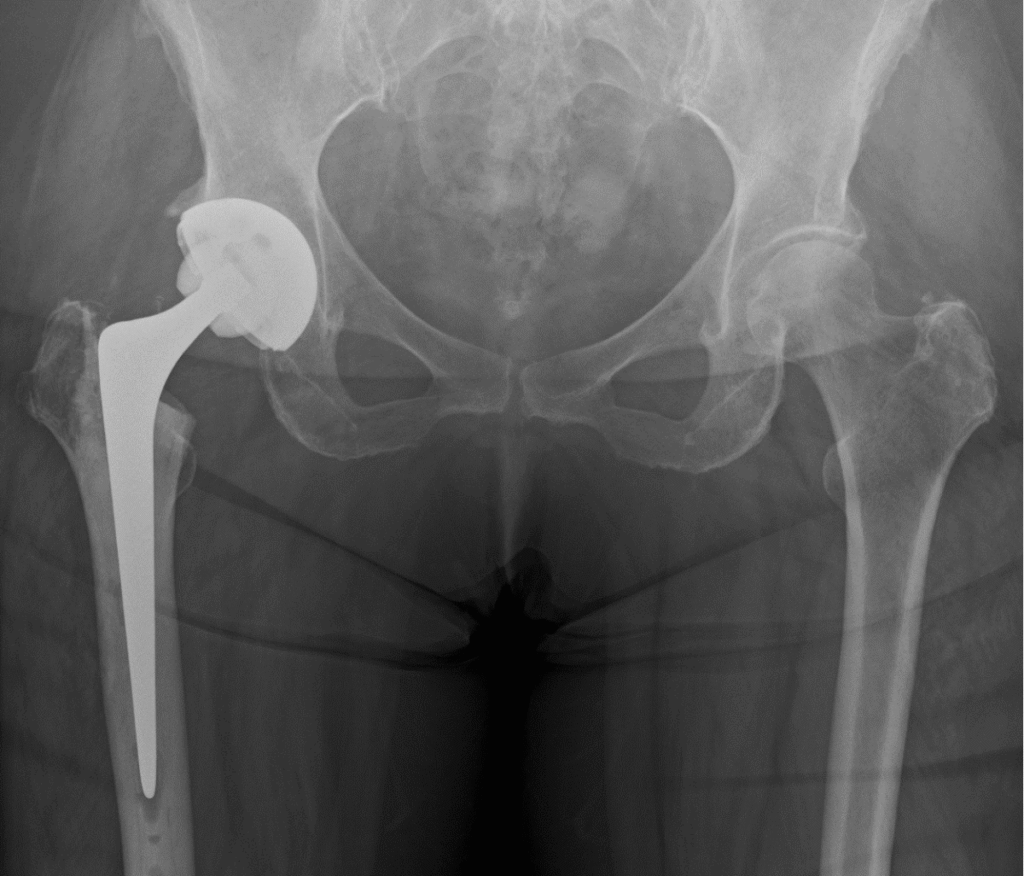

- X‑rays: The primary test to assess joint space, bone spurs and deformity.

- Advanced imaging: MRI or CT scans used selectively (for suspected avascular necrosis, unexplained pain, or pre‑surgical planning).

Mr. Radja offers modern techniques including muscle‑sparing approaches and robotic-assisted implantation where appropriate, which may improve precision and early recovery.

What to expect after hip replacement

- Day 0–1: Mobilise with physiotherapy; most patients start walking with aids.

- Weeks 1–6: Pain falls rapidly; continue physiotherapy to rebuild strength and gait.

- 6–12 weeks: Many return to light work and low‑impact activities.

- 3–6 months: Significant functional improvement and most daily activities achievable.

- 12 months: Full recovery and maximal improvement for most patients.

Recovery varies with age, fitness and the exact procedure performed.